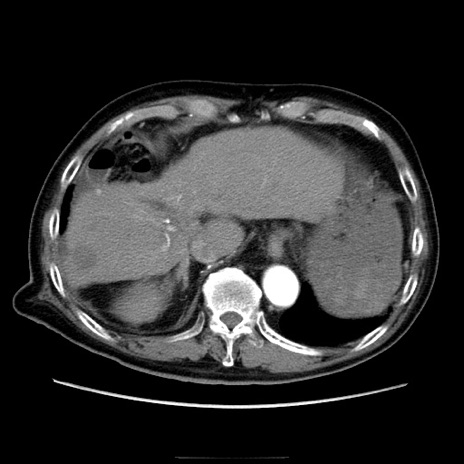

冠状断像

症例21(横断像)

【症例】70歳代男性

【主訴】腹痛

【現病歴】肝硬変・肝細胞癌にてかかりつけの方。約9時間前に食後より腹痛出現。症状が徐々に増悪し、嘔吐出現したため来院。

【既往歴】肝硬変、肝細胞癌(RFA、TACE後)

【身体所見】意識清明、表情苦悶様、BT 36℃、BP 129/78mmHg、P 88bpm、SpO2 97%(RA)、右上腹部から心窩部にかけて圧痛あり、反跳痛なし、筋性防御あり。

【データ】WBC 5800、CRP 0.16